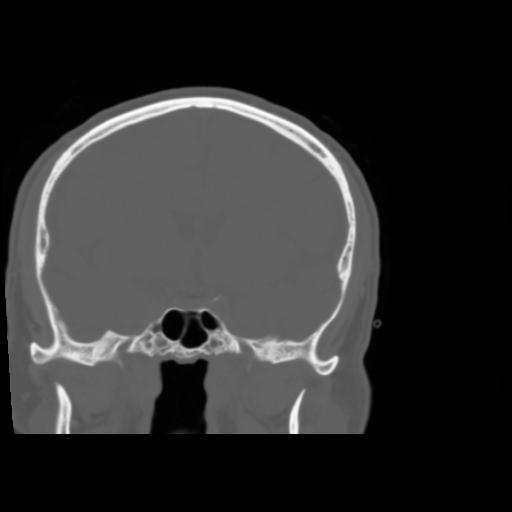

5 CEREBRO,,Coronal,3.000,CEREBRO,Coronal,